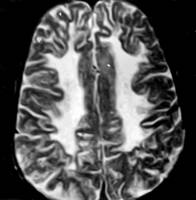

Modificari precoce in boala sunt cosiderate aparitia zonelor de hipersemnal, definitorii, pe imaginile cu predominanta T2 (fig. 2), cu precadere la nivelul substantei albe subcorticale occipitale mai mult decat a celei frontale. In majoritatea cazurilor, substanta cenusie este integra, chiar si in cazurile avansate.

Totusi TUNCAY si colab. au sesizat implicarea precoce a substantei cenusii, studiul lor evidentiind leziuni predominante la nivelul substantei cenusii si al substantei albe subcorticale (62). Leziuni descrise de ei sunt asimetrice si afecteaza preponderent partea posterioara a emisferelor cerebrale (fig. 3). Tardiv, ei au observat modificari de hipersemnal in structura profunda a substantei albe, si anumite grade de atrofie cerebrala. Leziunile parenchimatoase au fost corelate cu durata bolii.

Figura 3: imagine prin rezonanta magnetica avand

predominanta T2, prezentand zone hiperintense in ambele

regiuni occipitale.